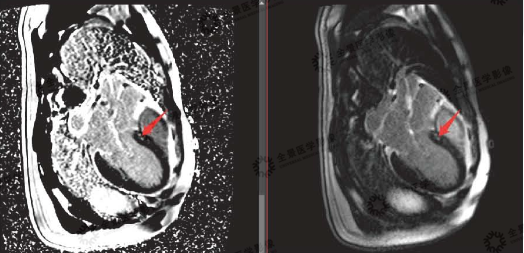

▲灌注序列

红色箭头:缺血区域充盈缺损表现

磁共振显示:该患者冠心病,心肌梗死,梗死心肌占左室总体60%,前降支供血区透壁性心肌梗死;右冠状动脉、旋支供血区基底部及中间段大部分心肌存活,心尖段心肌透壁性梗死。全心增大,心功能不全。